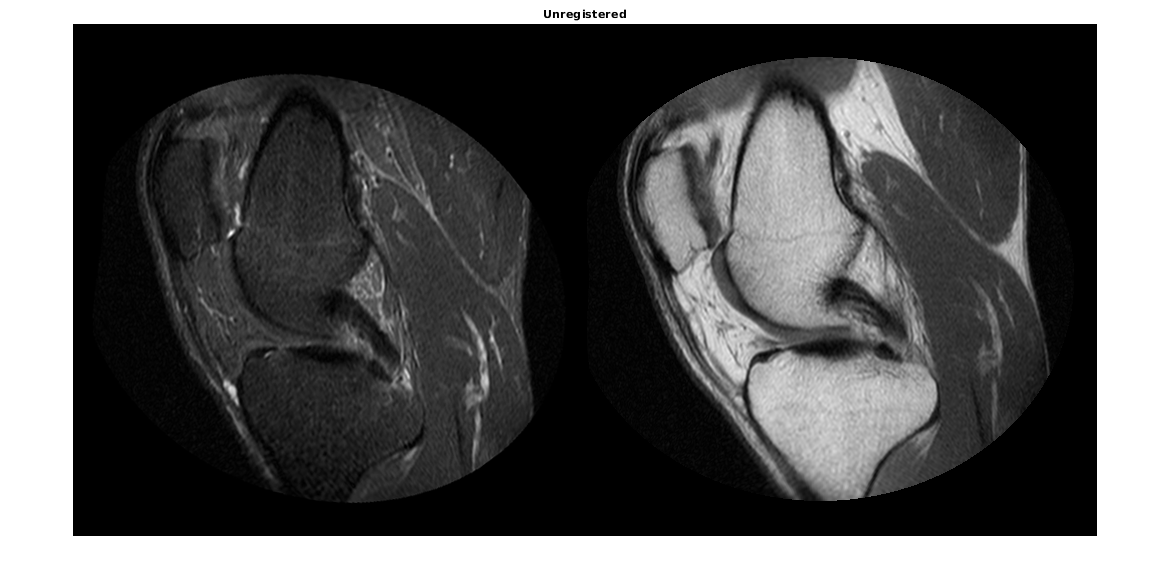

imshowpair функция полезна, чтобы визуализировать изображения во время каждой части процесса регистрации. Используйте его, чтобы видеть два изображения индивидуально способом монтажа или отобразить их сложенный, чтобы показать объем неверной регистрации.

imshowpair(moving,fixed,'montage') title('Unregistered')

В перекрывающемся изображении от imshowpair, серые области соответствуют областям, которые имеют подобную интенсивность, в то время как пурпурные и зеленые зоны показывают места, где одно изображение более ярко, чем другой. В некоторых парах изображений зеленые и пурпурные области не всегда указывают на неверную регистрацию, но в этом примере это просто в использовании информация о цвете, чтобы видеть, где они делают.

imshowpair(moving,fixed)

title('Unregistered')